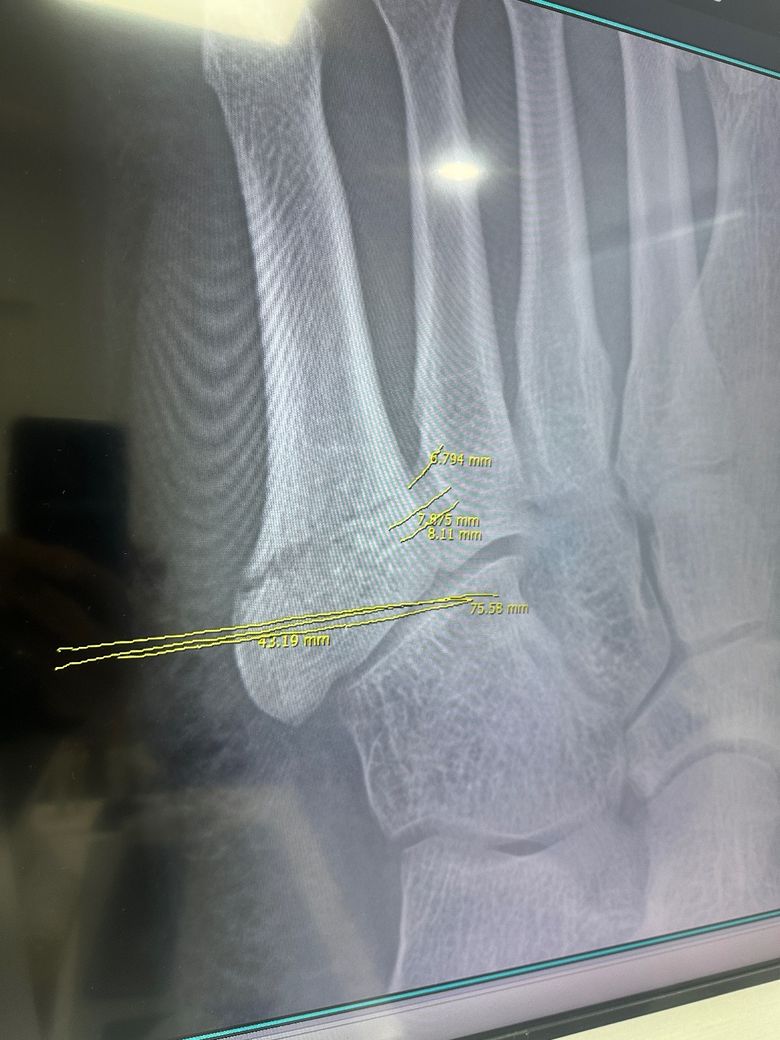

폐쇄성 중족골 골절 때문에 궁금합니다..

의뢰서에써있던 내용입니다

x ray 에서 FX. 5th MT base foot, Lt. (zone

0 환자로 환자 분, 보존적 치료 원하였으나, 3일 경과후 displacement 진행 양상으로 수술적 치료 권유 드린환자 입니다. 치료위해 진료의뢰 드립니다. 감사합니다.

• 1번 째 사진

5번째 중족골 기저부는 혈류가 약해서 자연치유가 잘 되지 않는 고위험 부위입니다. 특히 해당 부위 보존치료시 비유합이나 지연유합 위험이 높고 움직임이 많은 경우 뼈가 벌어져 오히려 더 안 붙을 수 있습니다.

보존치료가 가능하려면 골절 간격 2mm 미만, 환자 체중 부하 제한이 가능(목발을 6주 이상 사용할 수 있는 등)해야 하며 비흡연자, 당뇨나 순환장애가 없는 상태, 절대적인 침상 안정 유지 가능 등의 조건이 필요합니다. 하지만 3일만에 전위가 발생한 것으로 보아 불안정한 골절로 보이며 수술 없이 보존치료시 뼈가 붙지 않거나 비정상적인 위치로 붙을 수 있습니다. 그렇게 되면 나중에 오히려 더 큰 수술이 필요합니다. .